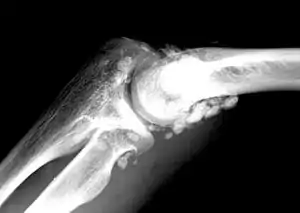

| X-ray of an elbow affected by synovial chondromatosis | |